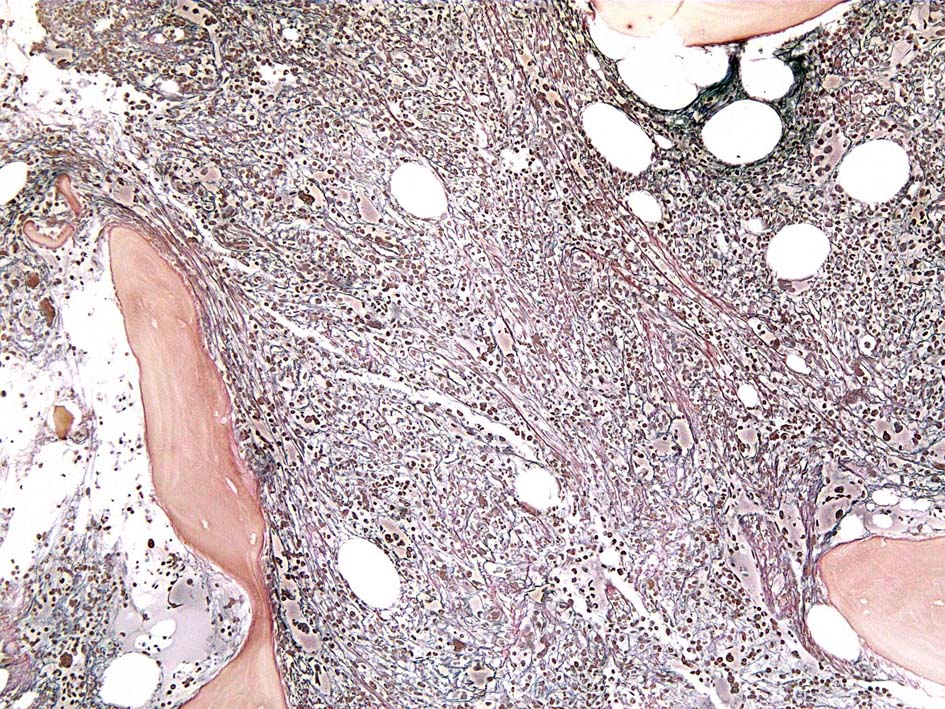

Case01; Meylofibrosis, overt fibrosis

77year-old female. 40歳時polycythemia veraと診断されていた.

[注] この症例は詳細は不明であるが, 過去にPVと診断されているため, PVに伴う二次性のmyelofibrosisの診断になる.

黒染する弾性線維の増生のほか, 赤く染まる膠原線維の増生が確認される. MF-2 fibrosis. 鍍銀染色の核染色をすると膠原線維の赤染がわからなくなるので行わない.